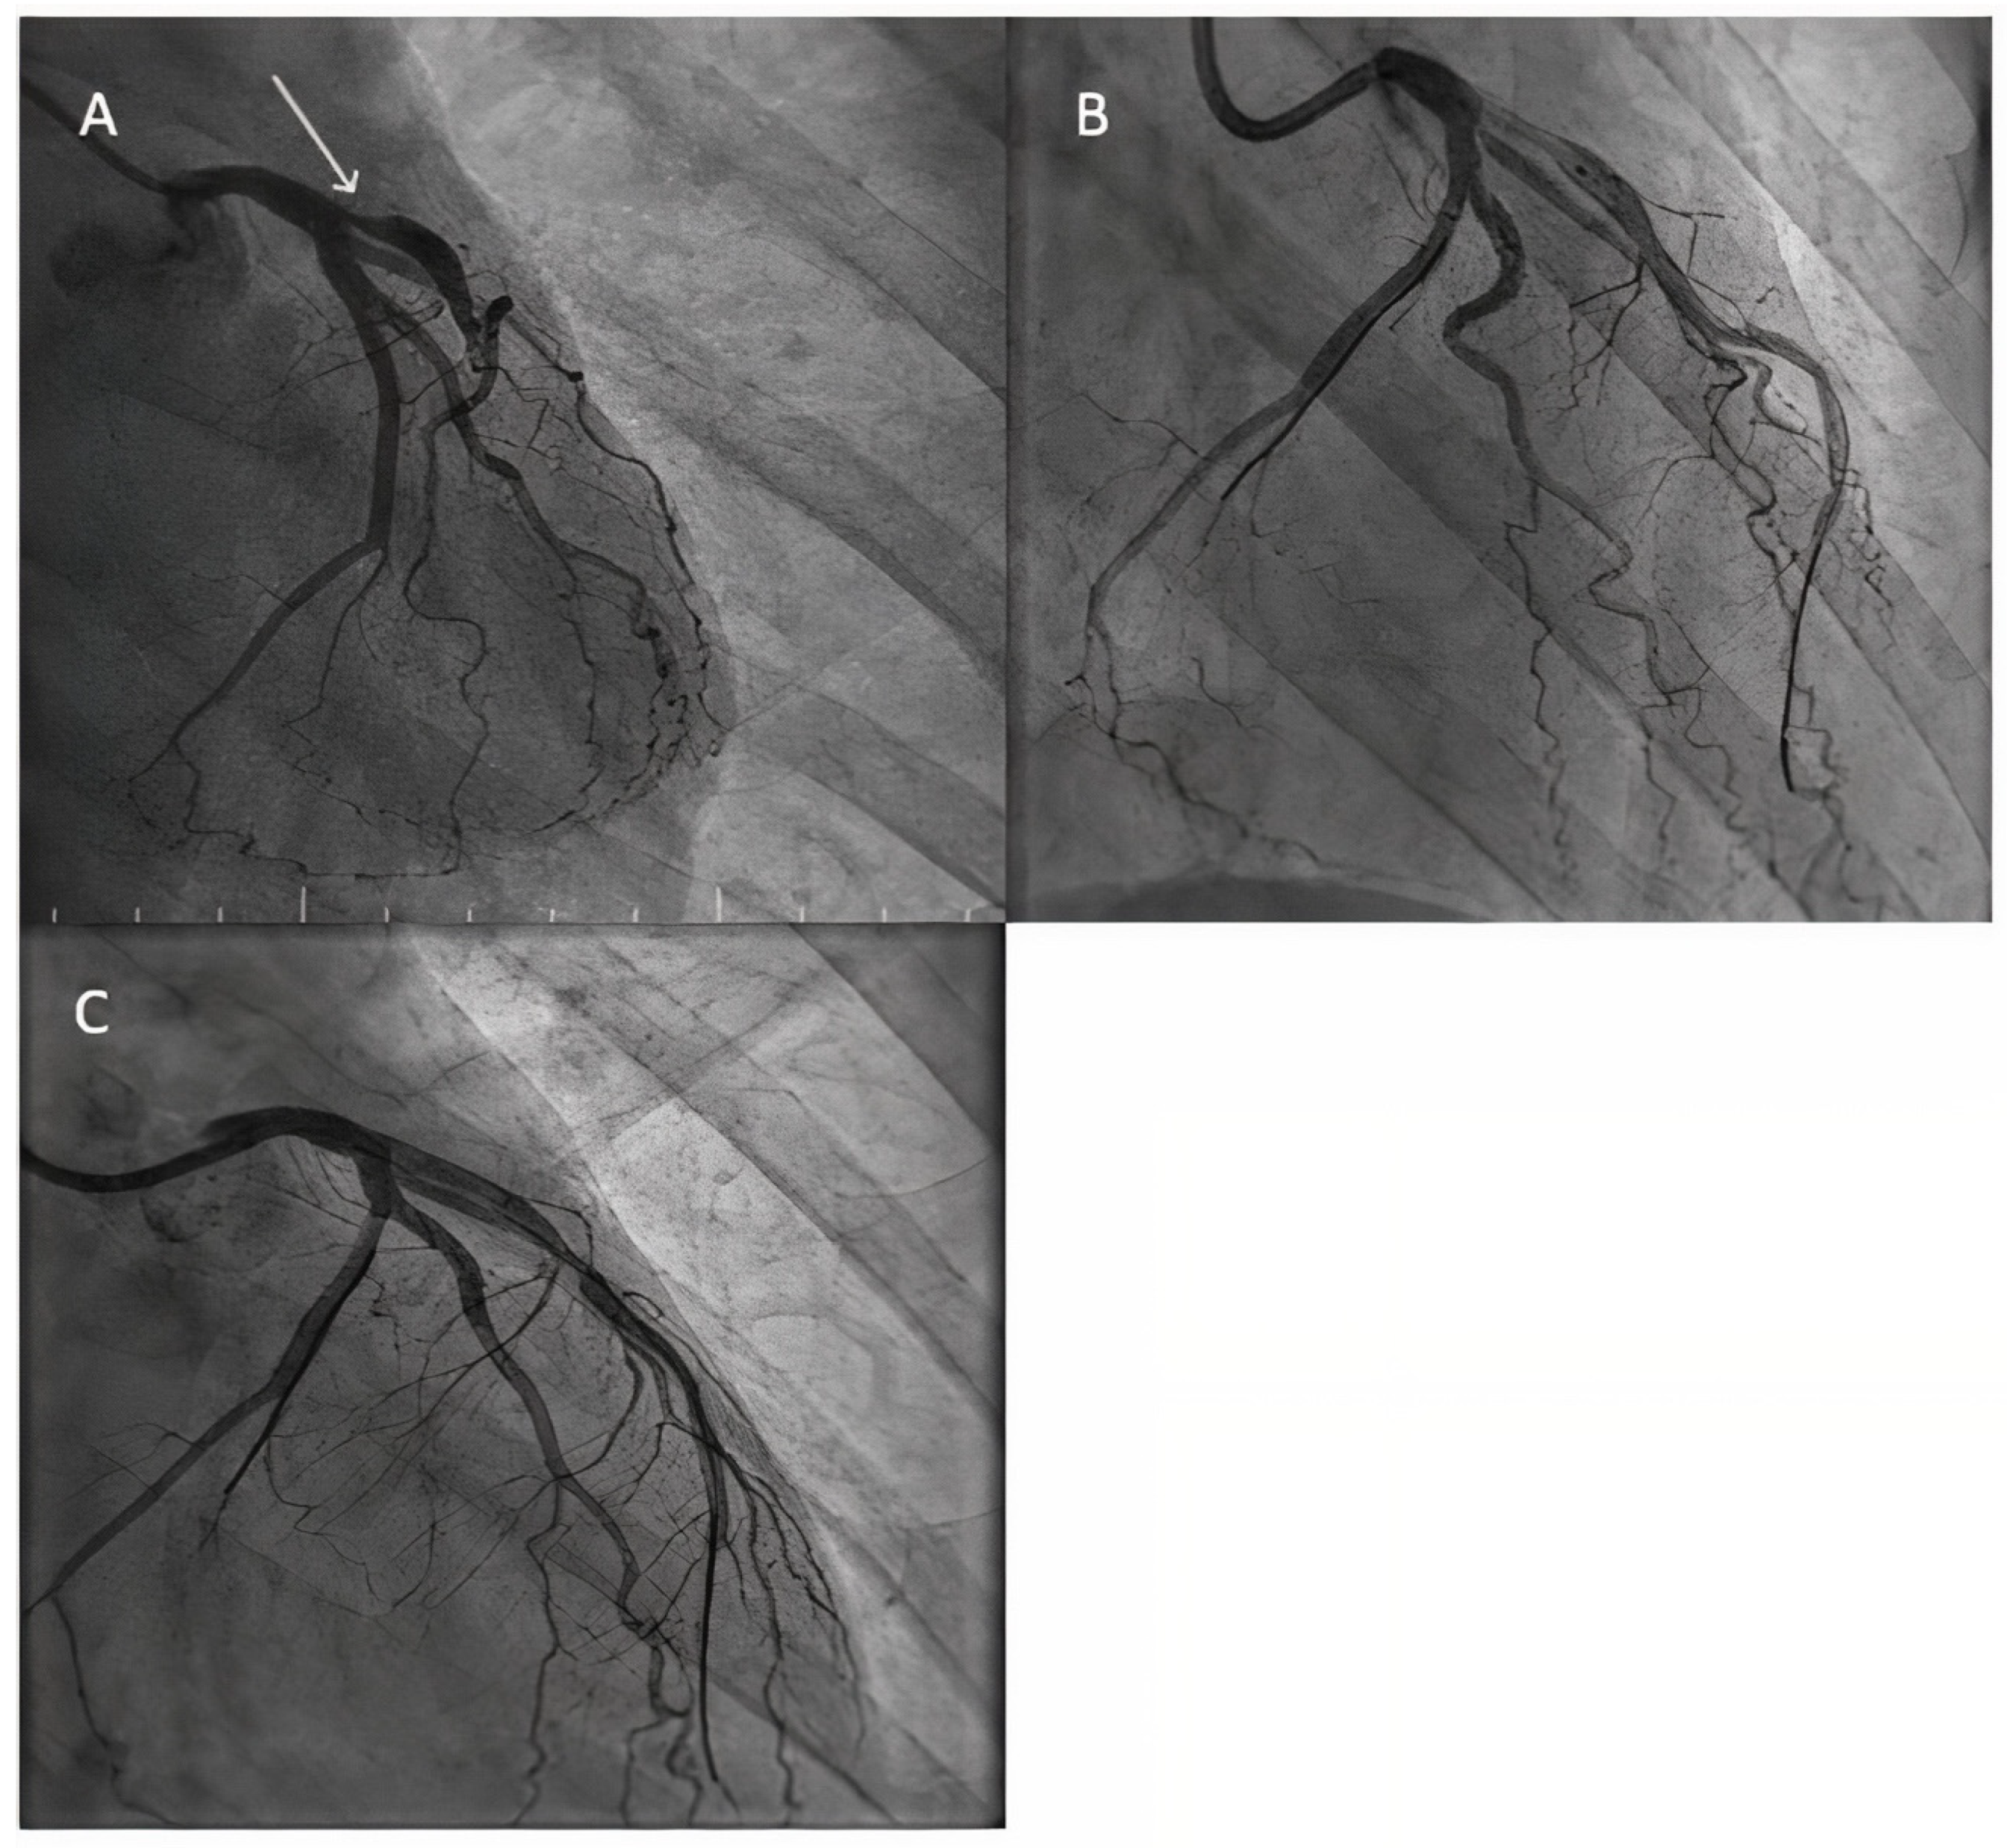

- Uskela, S.; Eranti, A.; Kärkkäinen, J.M.; Rissanen, T.T. Drug-coated balloon-only strategy for percutaneous coronary intervention of de novo left main coronary artery disease: The importance of proper lesion preparation. Front. Med. 2023, 17, 75–84. [Google Scholar] [CrossRef]